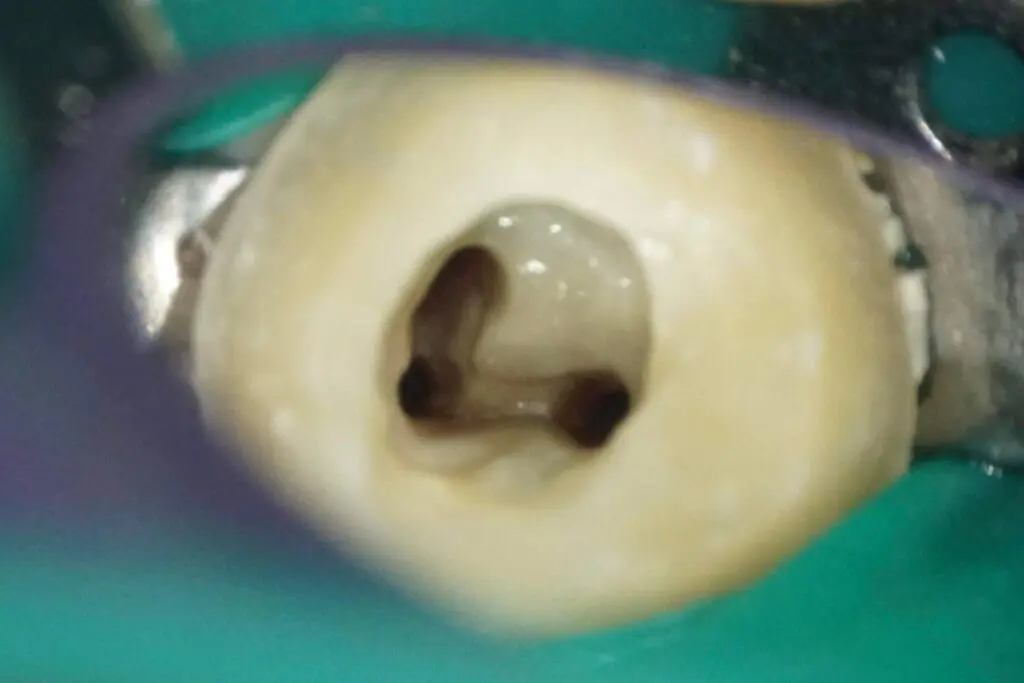

顯微根管治療前

牙科顯微鏡為醫師提供了完整的視野,那些傳統根管治療難以發現的根管也能精準的掌握。面對複雜的根管結構,顯微根管治療提高了治療的準確性,也增加了治療成功的概率。

根管清潔完成

根管清潔是為了徹底去除感染牙齒的細菌,為封填步驟做好準備。萊德美學牙醫分享,想在沒有牙科顯微鏡的輔助下徹底清潔這類的複雜根管並不容易,使用顯微根管技術清潔可以確保每個隱蔽的角落都被細致處理。

牙科顯微鏡為醫師提供了完整的視野,醫師可以清楚地看到患者牙齒內部的狀況。透過放大視野,牙醫師能夠更精確地定位根管,那些傳統根管治療難以發現的細小分支顯微根管治療也能精準的掌握。顯微根管治療不僅提高了治療的準確性,還大大增加了治療成功的概率,尤其是在多根管牙齒的治療上,能更保守、更完整地保存牙齒結構,為您的口腔健康打下堅實基礎。

根管清潔是根管治療中不可或缺的一部分,能夠徹底去除感染牙齒的細菌,為封填步驟做好準備。若根管清潔不夠徹底,殘留的細菌可能導致再次感染。尤其是像這個案例中的多根管牙齒,因為根管系統複雜,使用顯微根管技術清潔可以更精確、更全面,確保每個隱蔽的角落都被細致處理,避免未來的問題。